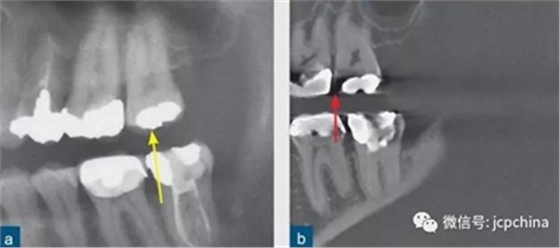

(a)根尖片。

(b)CBCT矢狀面。

同一解剖位置顯示出的廣泛射線硬化偽影,使CBCT分辨金屬邊緣變得困難。CBCT圖像中27牙的近中壁缺損可能為齲損(紅色箭頭),而根尖片(黃色箭頭)卻顯示正常。